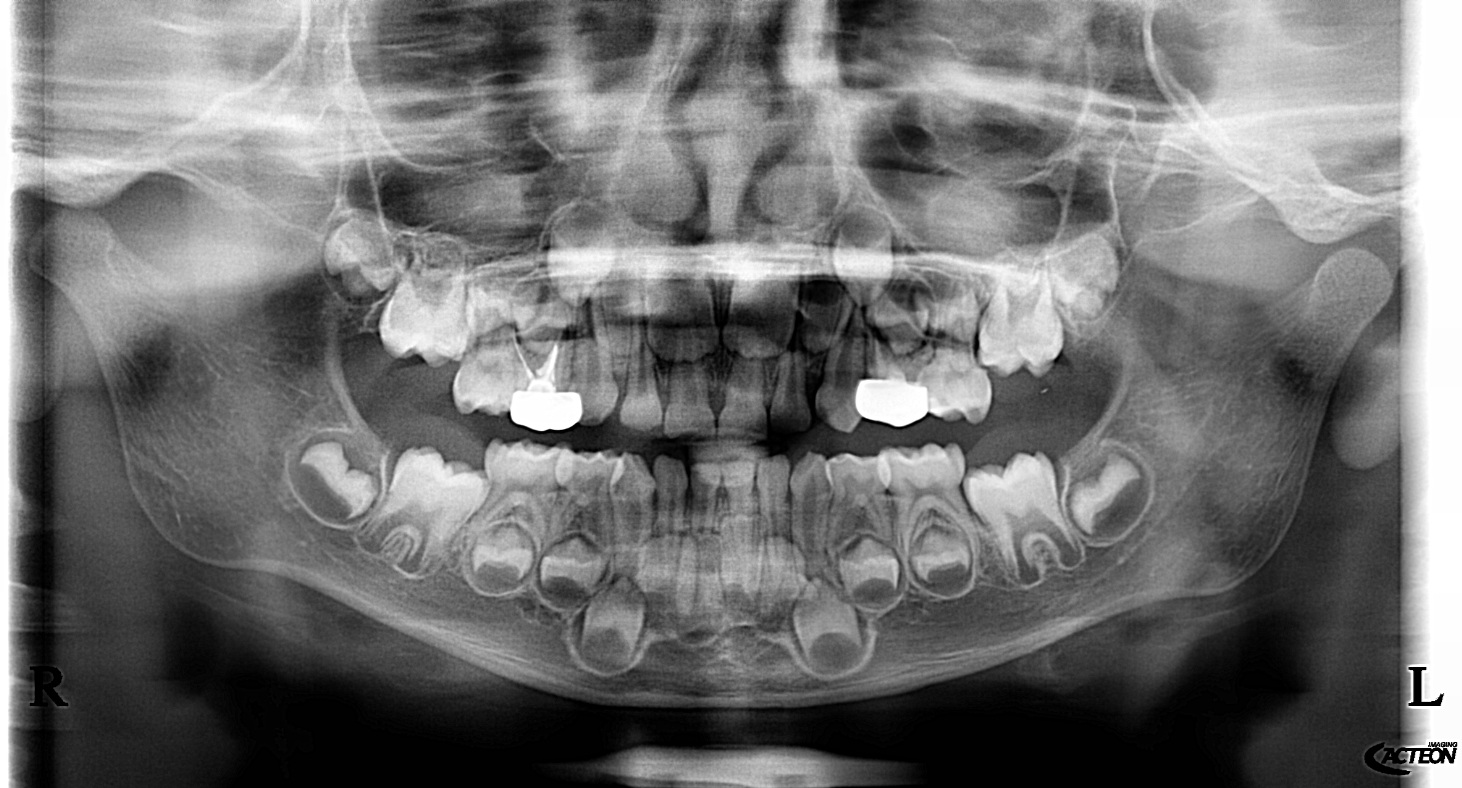

We use rotary nickel-titanium instruments, activated irrigation for deep disinfection, and modern bioceramic sealers for a dense, long-lasting seal. - Targeted diagnostics

We examine the tooth, test its response, and take focused images. When roots are complex or a previous treatment failed, a small 3D scan may be needed for mapping before we discuss and agree on the plan. - Anaesthesia and comfort